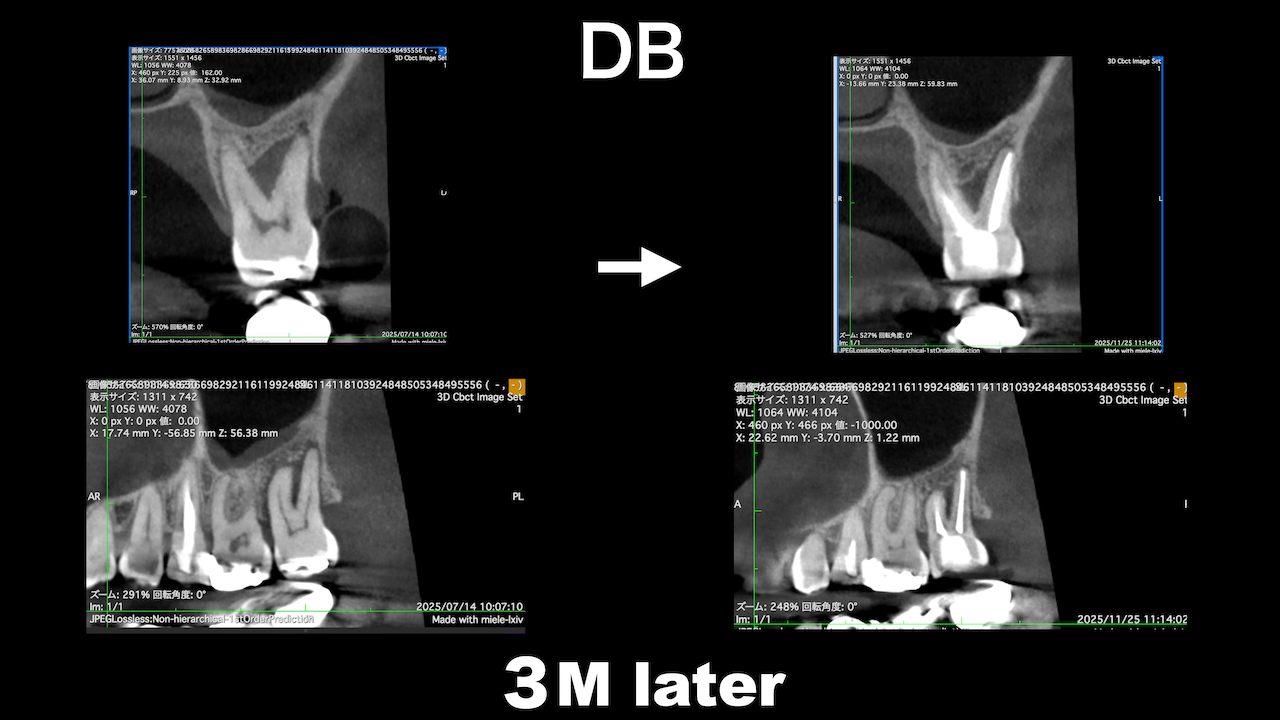

臨床的にDB

この後、

Sinus tractは消失した。

3ヶ月経過した。

DBの病変が小さくなっている。

Pは病変が大きくなっていうように見えるがまだわからない。